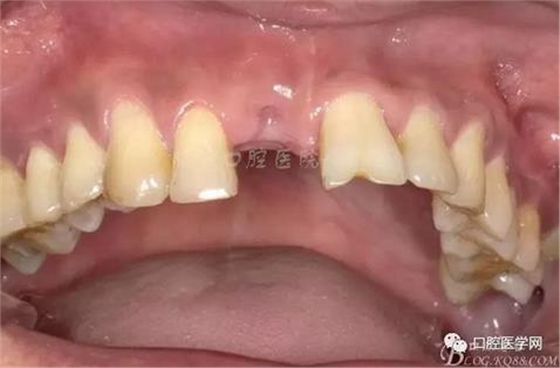

圖4 術(shù)前正位頜面照